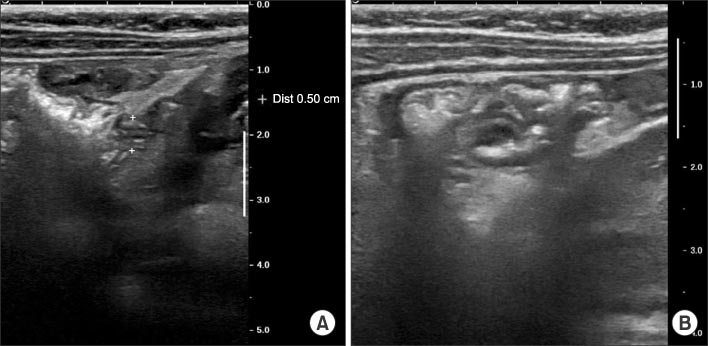

We immediately conducted abdominal X-ray and gastrointestinal ultrasonography for rule out of intussusception. But, there was no evidence of intussusception or appendicitis on gastrointestinal ultrasonography, with small amounts of fluid collection around small and large bowel (Fig. 1).

Fig. 1

Gastrointestinal ultrasonographic images show normal range of appendix intact (diameter 0.5 cm) (A) and intact ileocecal valve (B).

Fig. 1 Gastrointestinal ultrasonographic images show normal range of appendix intact (diameter 0.5 cm) (A) and intact ileocecal valve (B).